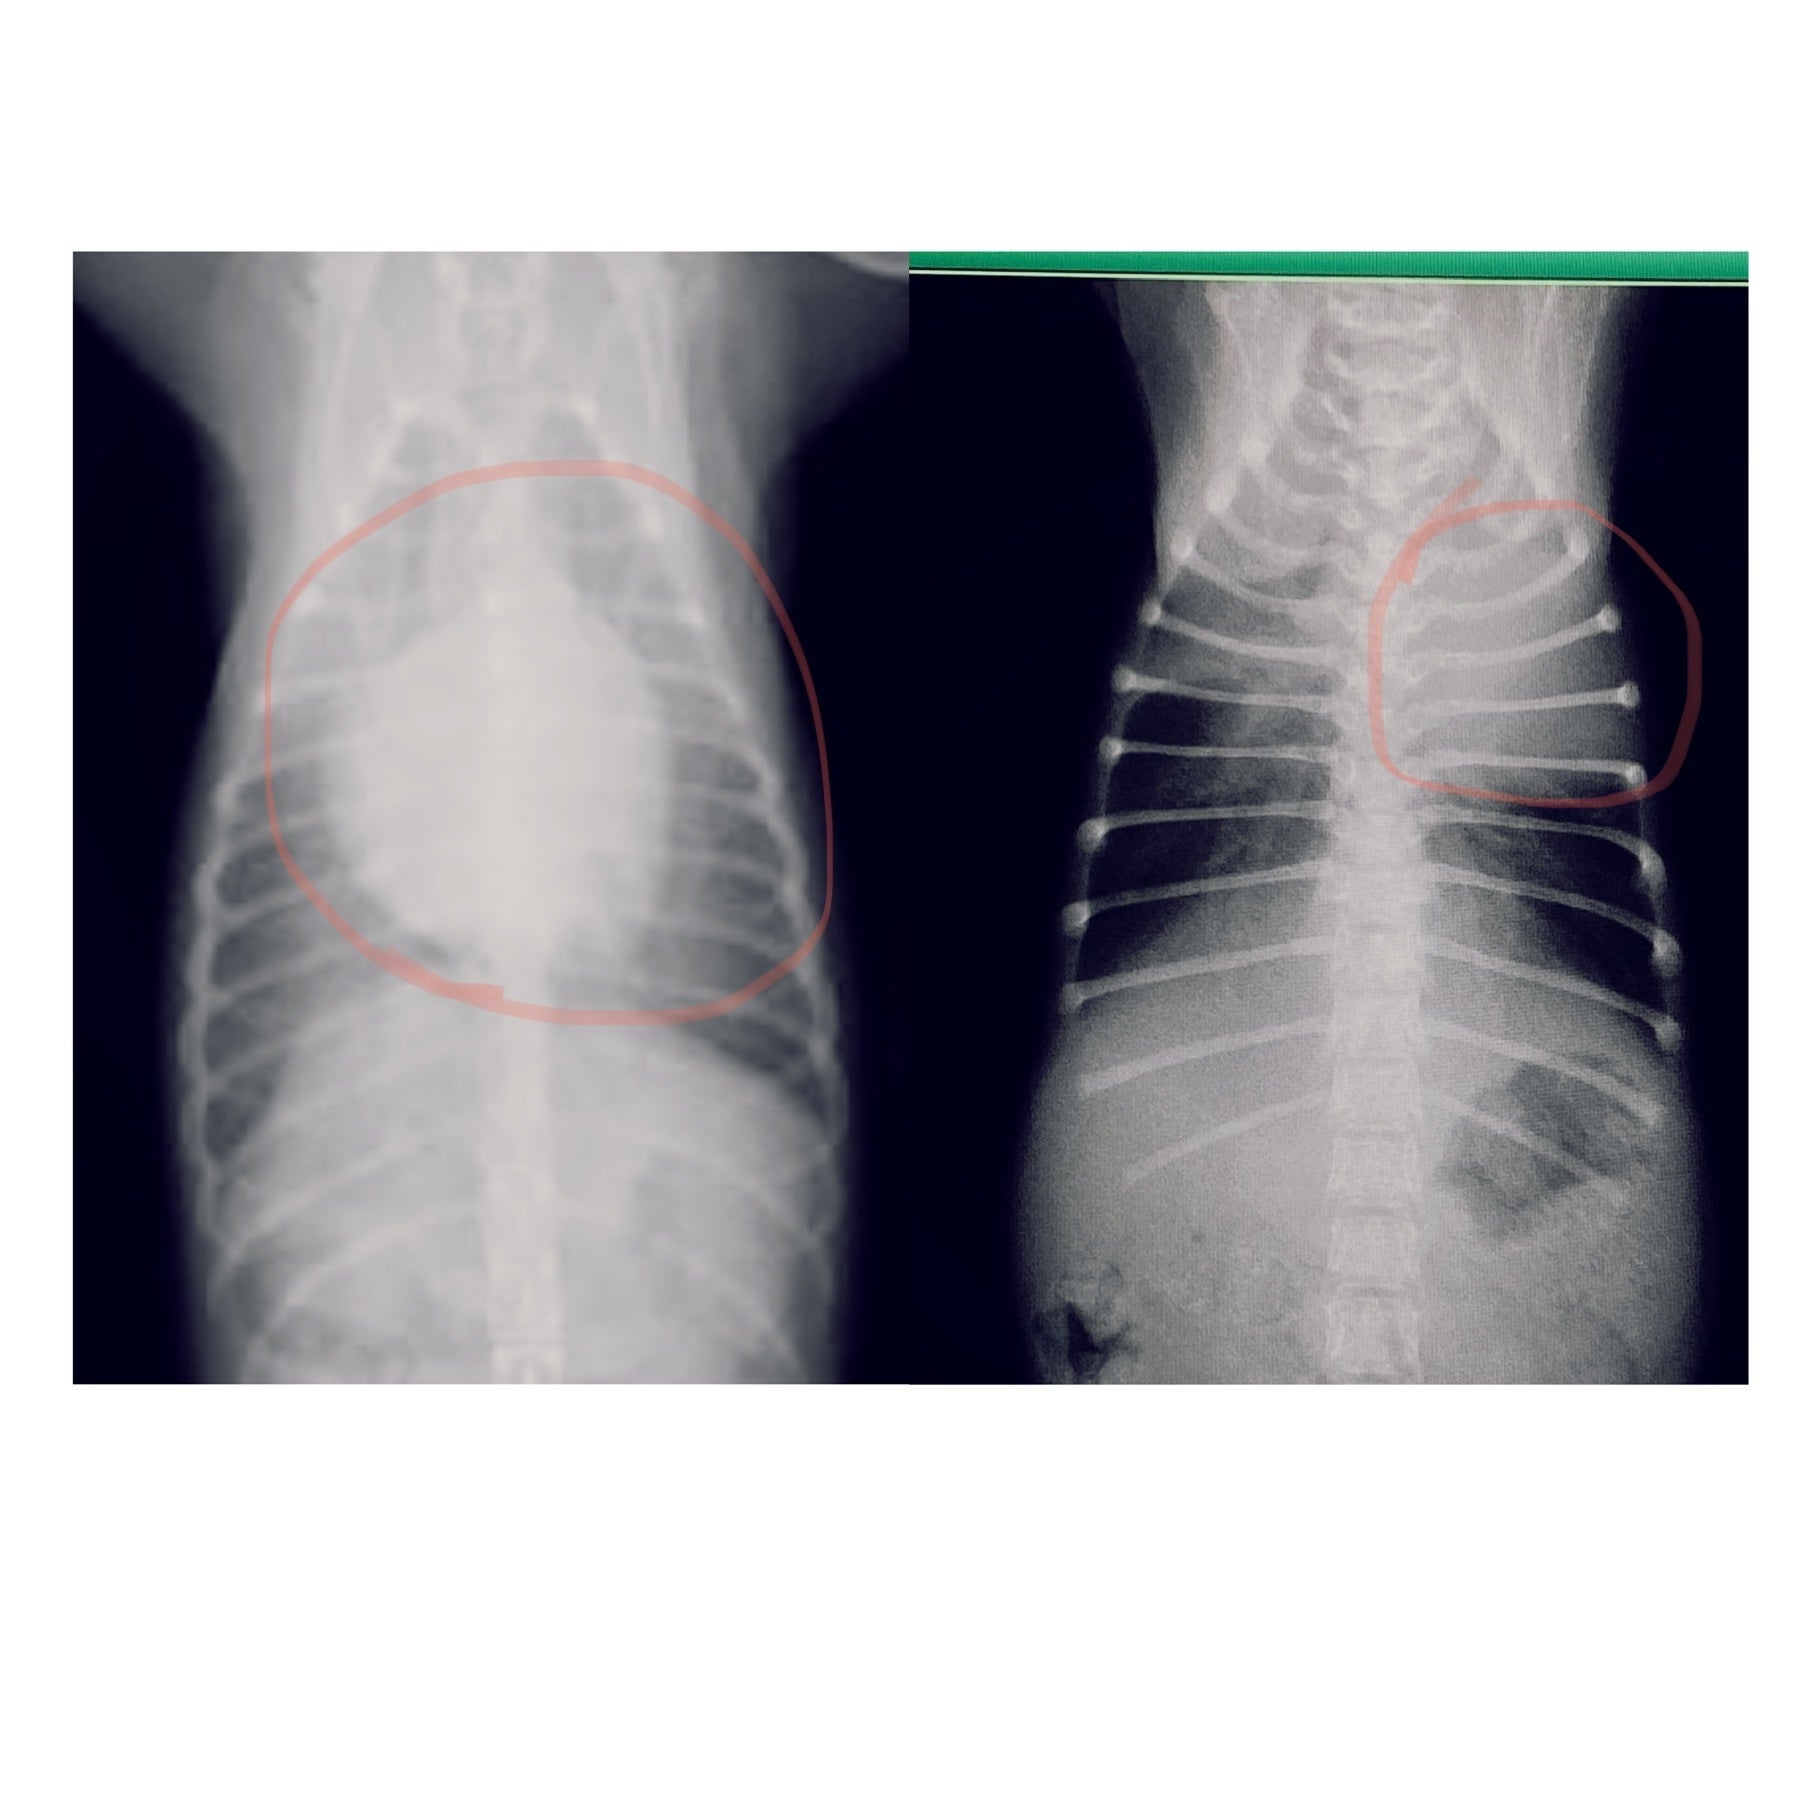

左が通常の子のレントゲン、右がうどんちゃんのレントゲンです。

赤丸の中心が心臓ですが、通常と大きさと位置が大きくズレていることが分かると思います。

肋骨も庇うためか歪んでしまっていました。。